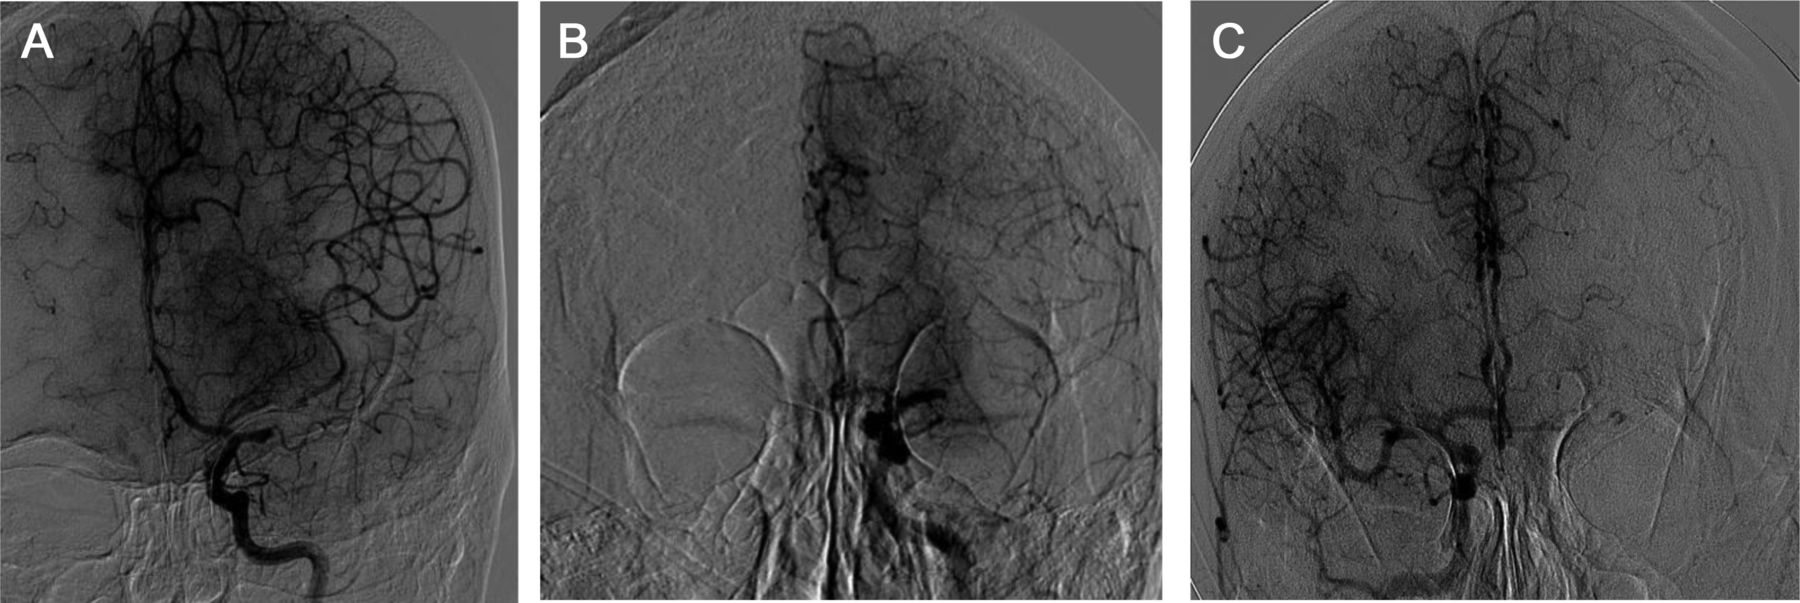

图2 络脉在血管摄影的例子

优秀的4级络脉,填满整个大脑中动脉(MCA)领土(一个);三年级担保物(B),填充MCA的大部分领土在同侧颈内动脉(ICA)注射;和二年级担保物(C),填充MCA领土虽然前动脉和大脑前动脉在交流侧ICA注入。